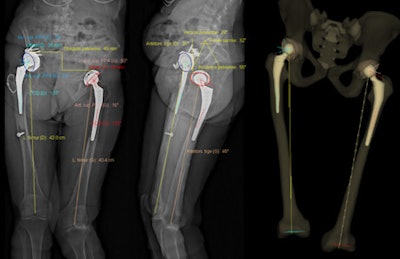

"In a single acquisition period, this 3D SR system also determined the valgus and varus measurements of the weight-bearing lower limbs. This too should reduce the patients' medical irradiation a little more, by avoiding the need for other medical imaging," noted lead author Dr. Cyrille Delin, from the Réseau d'Imagerie Médicale Maussins-Nollet in Paris. "The use of the SR system to study the torsion of lower limbs makes it possible to reduce the amount of medical irradiation that patients accumulate."

An example of 3D modeling performed with the EOS system for the assessment of total hip arthroplasty. Image courtesy of Dr. Cyrille Delin.Relatively few published studies have sought to optimize the dose received by patients during exploration of the lower limbs, particularly the hips, so thestudy team sought to calculate and compare the doses of ionizing radiation delivered to the organs by CT and SR during measurements of lower limb torsion and anteversion.

"Lower limb torsion values (anteversion of femoral necks or torsion of the knees or legs) play a role in the functioning of these limbs and in the development of osteoarthritis of the hip," they stated. "These values must be measured before placement of hip or knee prostheses but also before osteotomies for femoral or tibial correction of bone calluses or dysmorphisms. They are also useful before surgical revision of hip and knee prostheses in cases of poor positioning, given the frequent imprecision of surgeons' intraoperative evaluation of prosthetic femoral anteversion."